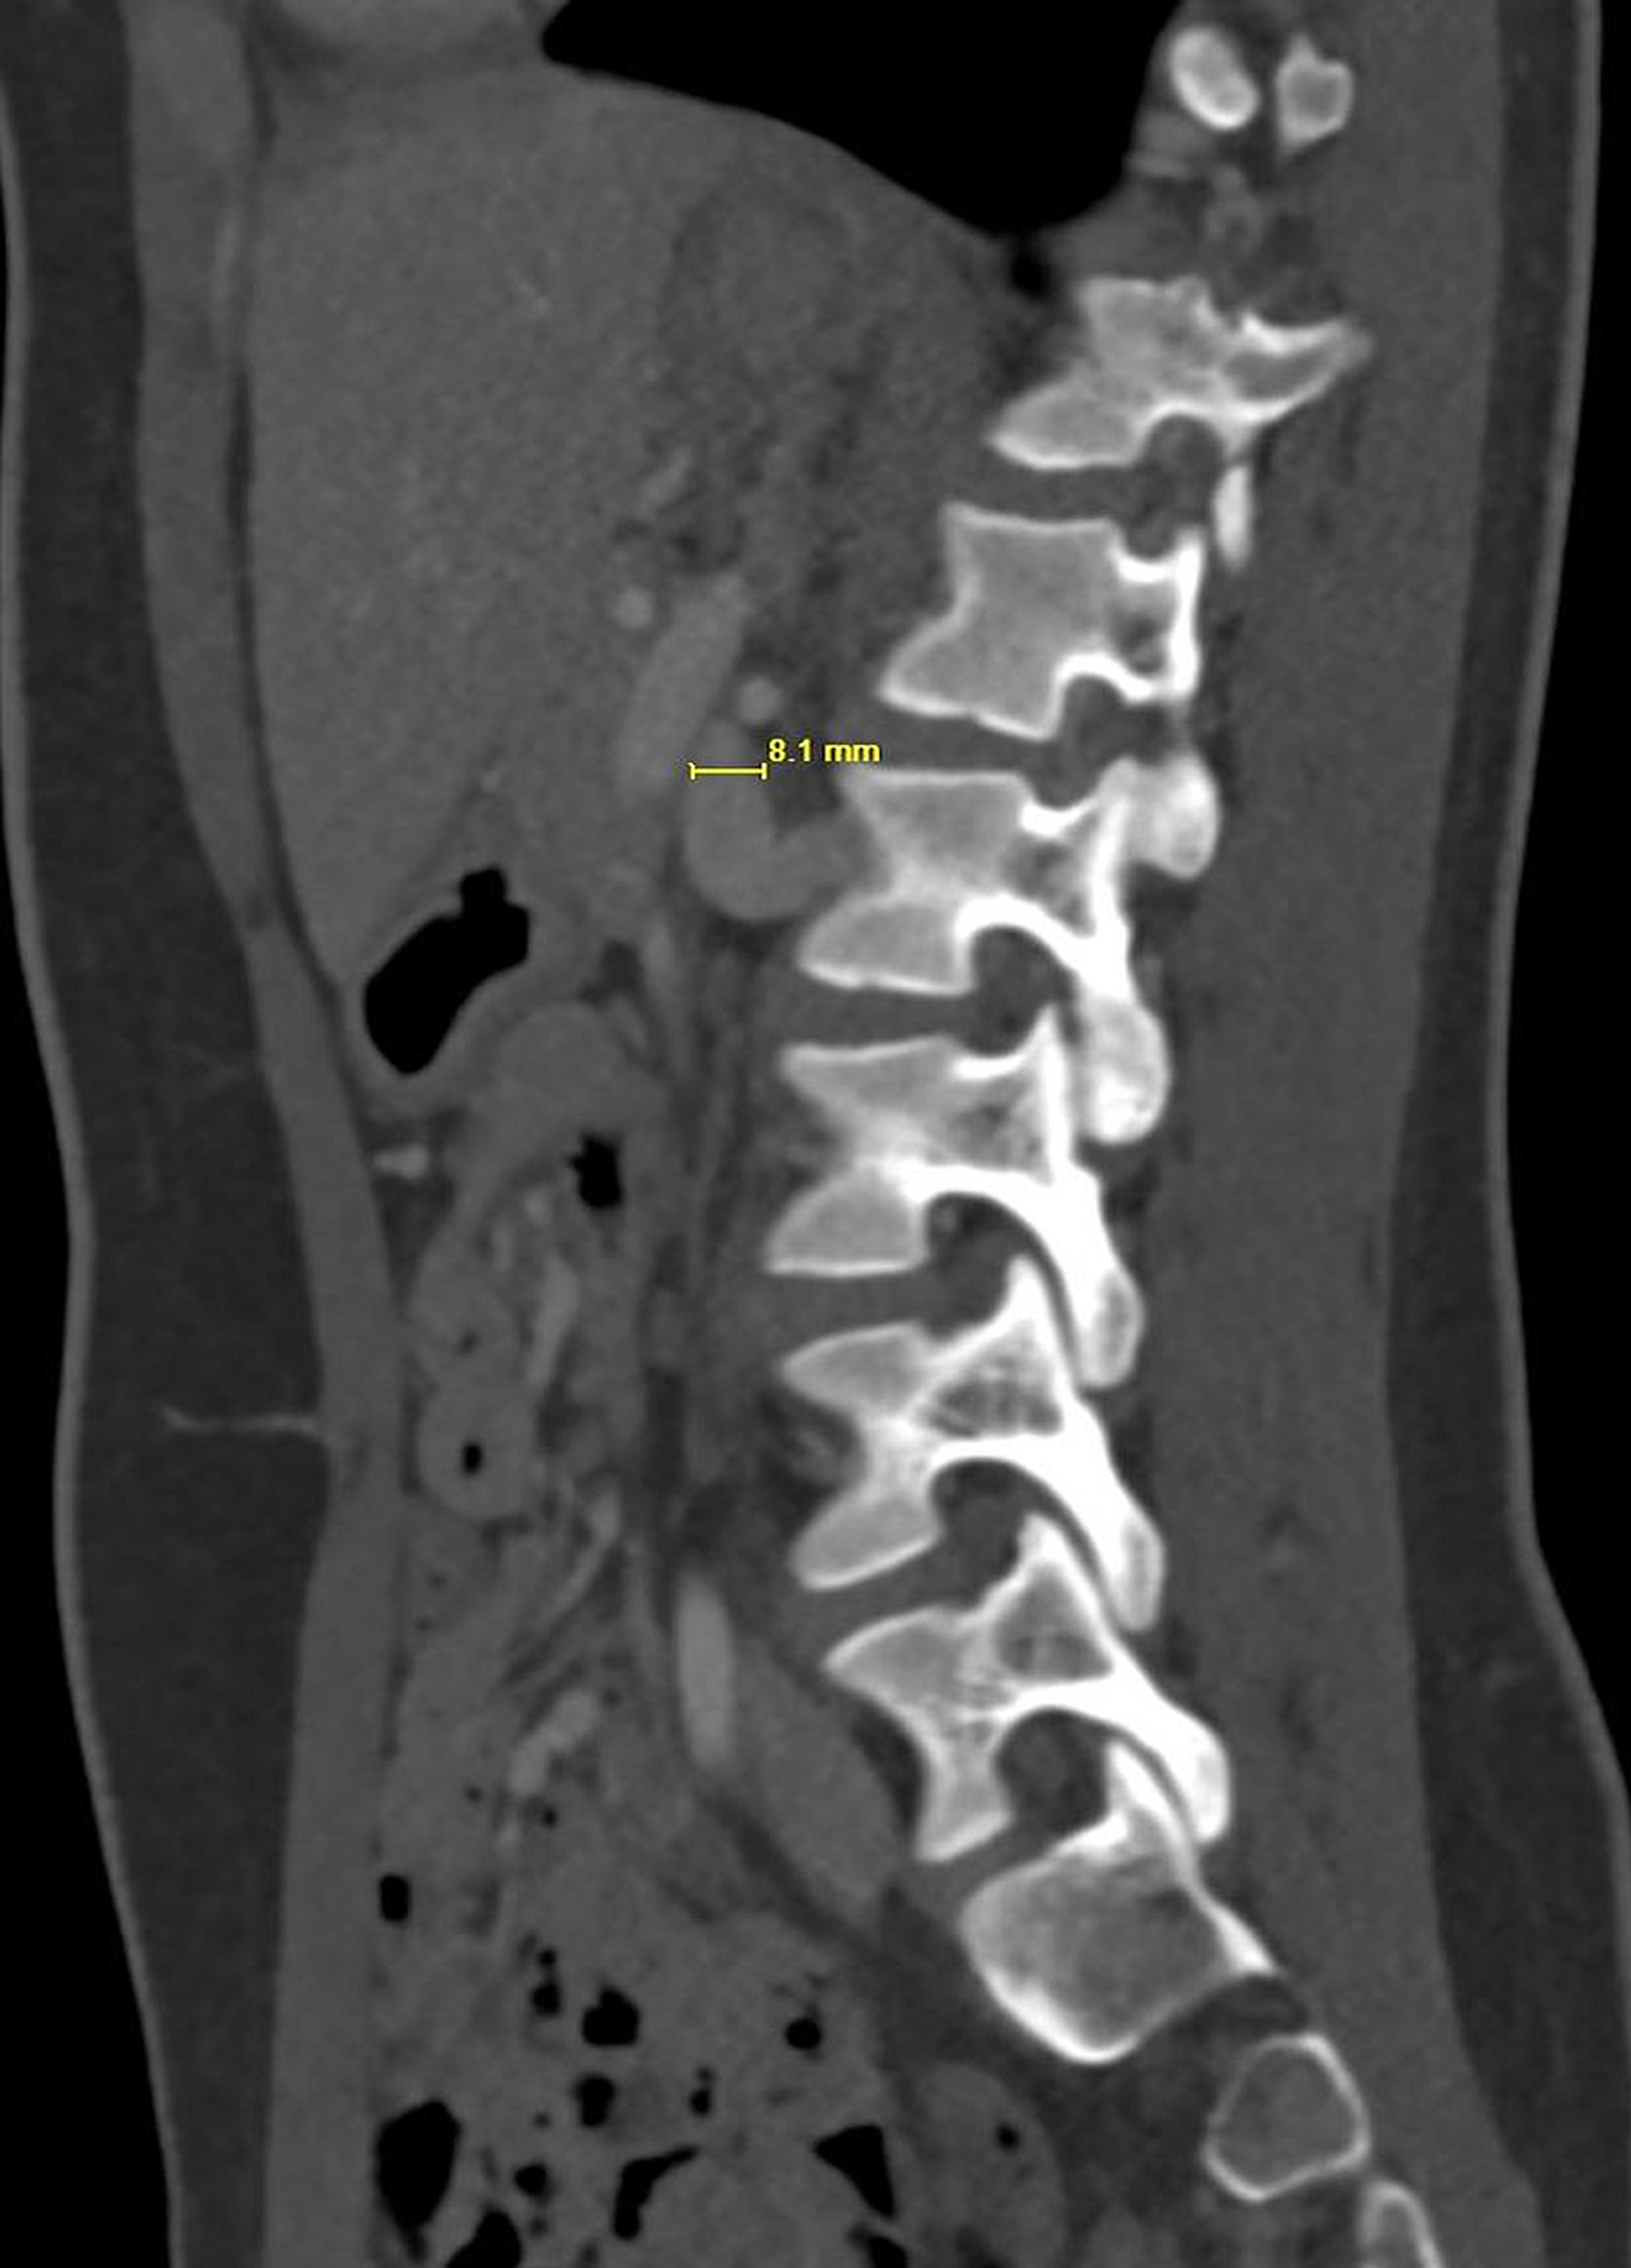

CT Angiography of Posterior Nutcracker Syndrome Radiology Nutcracker Syndrome Abdominal Pain Operative intervention should be considered for adults with gross hematuria, especially for patients requiring transfusion or with recurrent episodes, and for patients with such severe flank or abdominal pain that narcotic pain medication or hospitalization is required. Nutcracker syndrome (ncs) is an extrinsic compression of the left renal vein (lrv) by the superior mesenteric artery (sma). Nutcracker syndrome (ncs) is. Nutcracker Syndrome Abdominal Pain.

CT Angiography of Posterior Nutcracker Syndrome Radiology Nutcracker Syndrome Abdominal Pain The nutcracker syndrome is a rare clinical entity caused by compression of the left renal vein (lrv) by the superior mesenteric. The most common clinical presentations of ncs include pelvic pain, flank pain, haematuria, and gonadal varices (varicocele or ovarian vein syndrome, fig. Nutcracker syndrome (ncs), a rare but impactful vascular condition, emerges from the compression of the left renal. Nutcracker Syndrome Abdominal Pain.